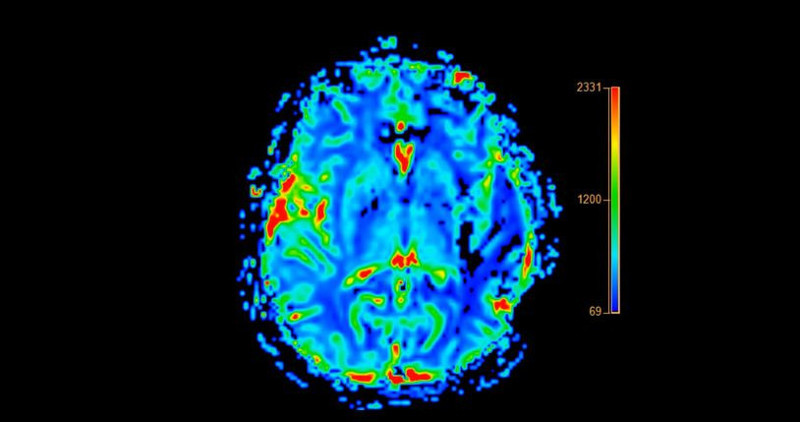

Araştırmalarda koku tanıma testi, bilişsel bozukluk ve demans tanısı için kullanılan iki biyolojik belirteç ile karşılaştırılmıştır. Bulgular bilişsel bozukluk ve demansı saptamada koku tanıma bozukluğunun, MR kullanarak ölçülen entorhinal korteks kalınlığı kadar, hatta daha da iyi bir belirteç olduğunu göstermiştir.

Buna karşın koku testi beyinde amiloid plakları gösteren Amiloid PET kadar etkin bulunmamıştır. Ancak, PET incelemeleri koku tanıma testine kıyasla son derece maliyetli ve uygulanması zordur. Daha ileri araştırmalar koku alma testinin demans riskini erken dönemde saptamada kullanışlı bir testi haline gelmesini sağlayabilir.”